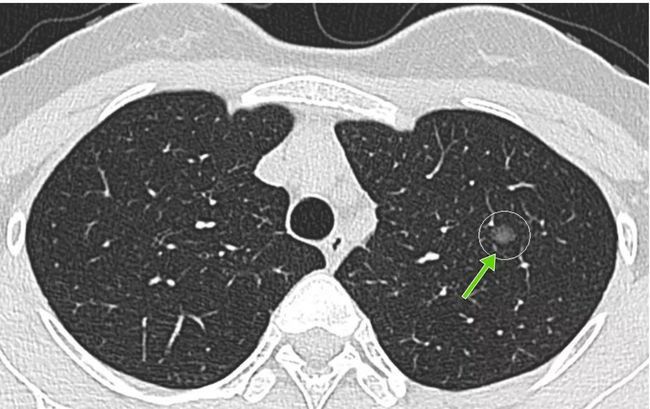

结节大小:

一般来说 , 直径小于5mm的肺结节恶性概率低于1% , 超过2cm的肺结节恶性概率高达64%~82% , 如果实性结节超过1.5cm , 或者部分实性结节大小超过8mm , 其恶性的概率较高 。

结节形质:

【成都中医哮喘病医院|体检若发现肺结节怎么办?不要慌,大多数结节都是小问题】1. 实性结节 。 尤其是小的实性结节 , 多属于良性结节 , 高密度、均匀 。

2. 磨玻璃结节 。 小于8—10mm多属于良性结节 , 看起来淡淡的 。

3. 混合结节 。 部分磨玻璃、部分突变 , 恶变率为60%以上 。